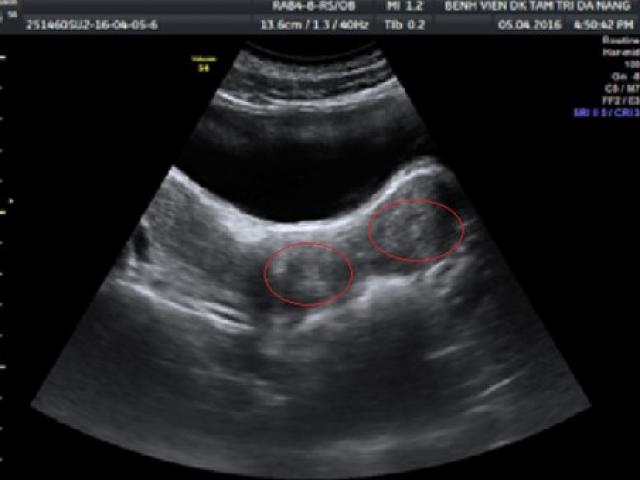

Theo bác sĩ, vết muỗi cắn trên mũi của Matthew thực chất là một khối u. Khối u này chính là dấu hiệu của bệnh ung thư mô liên kết, một là loại ung thư hiếm gặp trong các mô liên kết của cơ thể. Mỗi năm chỉ có tối đa 10 người tại Anh mắc phải căn bệnh ung thư này.

Khối u đã phát triển lớn và di căn về phía mắt và phần môi của cậu bé nên không thể thực hiện điều trị bằng xạ trị thông thường. Vì vậy Matthew được chuyển đến bệnh viện chuyên môn ở Mỹ.